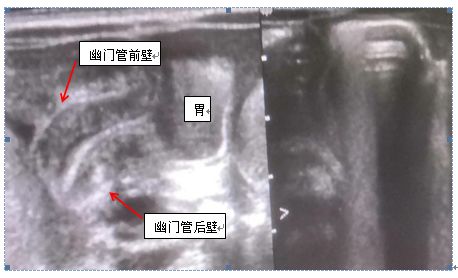

结果显示:患儿幽门管壁明显增厚,前壁厚约6.1mm,后壁厚约5.4mm,长度约23mm,吴颢主任慎重考虑后结合患儿病史,诊断为先天性幽门管肥厚性狭窄。(如上图)同期头颅MRI及脑脊液结果回报阴性,遗传代谢疾病筛查未示异常。

先天性肥厚性幽门狭窄是由于幽门环形肌增生肥厚,使幽门管腔狭窄,从而引起上消化道不完全梗阻。该病发生率约1/3000~1/1000,占新生儿先天性消化道畸形第三位,第一胎多见,男性多见,且病因尚未完全明确。该病一般出现在新生儿生后2~4周,也有迟至2~3月发病。主要表现为进行性加重的频繁呕吐,呈喷射状,但呕吐物不含胆汁,部分患儿上腹部还可触及肿块。频繁呕吐导致孩子体重不增、脱水、休克,严重影响孩子的生长发育。超声检查作为一种实时、便捷、安全的检查手段,为诊断先天性肥厚性幽门狭窄的首选检查。正常幽门管在超声图像中上壁厚度<4mm,管腔内径>2mm,长径≤16mm,内应充满气体,呈强回声。